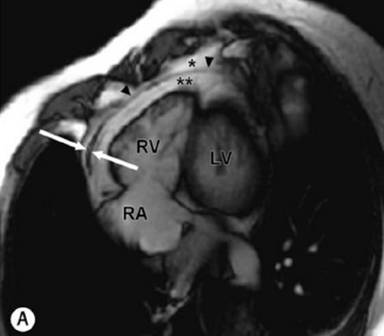

SSFP gradient-echo white blood cine images in modified four-chamber view

Black-blood fast SE sequence without fat suppression

cine (SSFP) CMR ,nonspecific overall thickening of the pericardium (black

arrow)

on contrast-enhanced CT enhancement of both outer

parietal and inner visceral layers of the pericardium due to inflammation (white arrow) with interposed mild effusion.